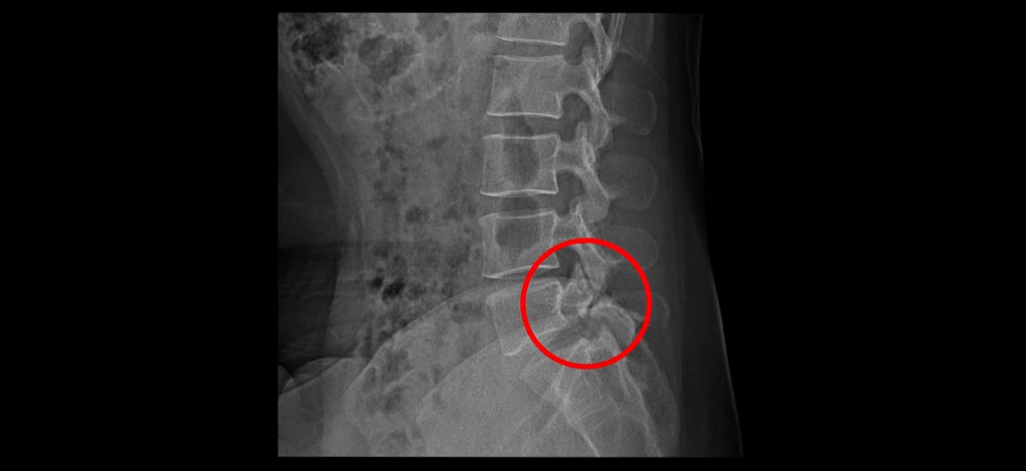

그런데 이 환자분의 X-ray를 보면 척추분리증으로 인한 전방전위증과 불안정성이 있습니다.

허리를 구부렸다 폈다 할 때 허리 신경 공간의 변화가 있음을 유추해 볼 수 있습니다.

그러나 전방전위증이 조금 있다는 이유만으로 섣부르게 나사 박는 유합술까지 하기에는 수술 예후가 불확실하니 환자분은 너무 불안해 하셨습니다. 그래서 열심히 인터넷과 유튜브를 뒤져 저희 병원을 찾아보시고 전화를 주신 건데요. 전화 상담 결과 마비가 발생한지 얼마 되지 않았다는 점, 또 무거운 걸 들다가 허리 통증, 다리 방사과 함께 찾아온 마비 증상이라 허리 문제일 가능성이 매우 높다는 점, 이런 이유로 저희 비수술 치료로 마비가 회복될 가능성이 높다는 것을 설명해 드렸고 서울로 올라와서 입원 치료 받으시라고 권유해 드렸습니다.